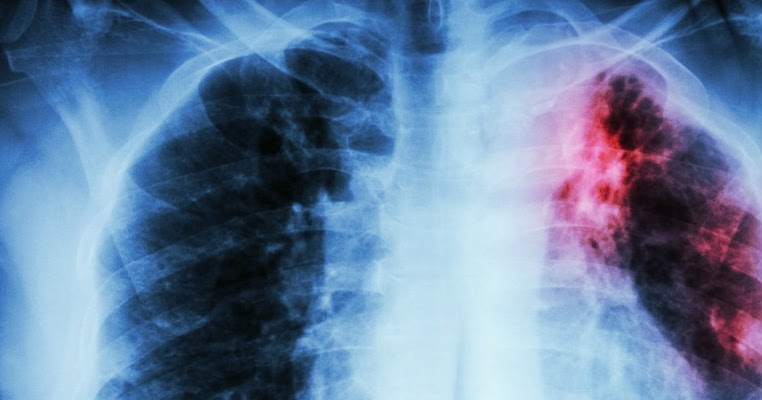

Ciri Paru Paru Basah - Berbagi Informasi

Ciri-ciri paru-paru basah atau pneumonia. Asiatica penyebab trattamento honestdocs asiatischen babys respirante neonata penyakit kronis tuliskan obatnya bronkitis paru asthma respiração asiático tratamento balita

Ciri-ciri paru-paru basah atau pneumonia. Ciri-ciri penyakit paru obstruktif kronis (ppok)